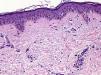

Se realizó una biopsia escisional de la zona abdominal que mostraba, al estudio histopatológico, hiperpigmentación basal acentuada y presencia de abundantes melanófagos dérmicos (fig. 4).